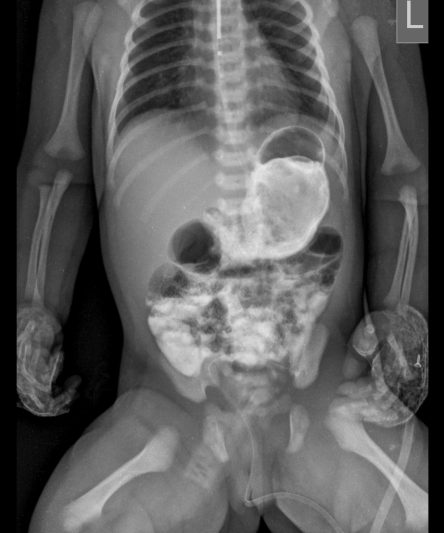

Microskan with Ultra high frequency can take the Lateral Lumbar Spine image of a 90 kg Patient with the correct image receptor